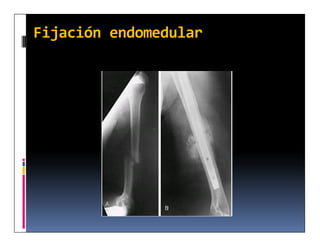

Fijación endomedular

Clavo endomedular